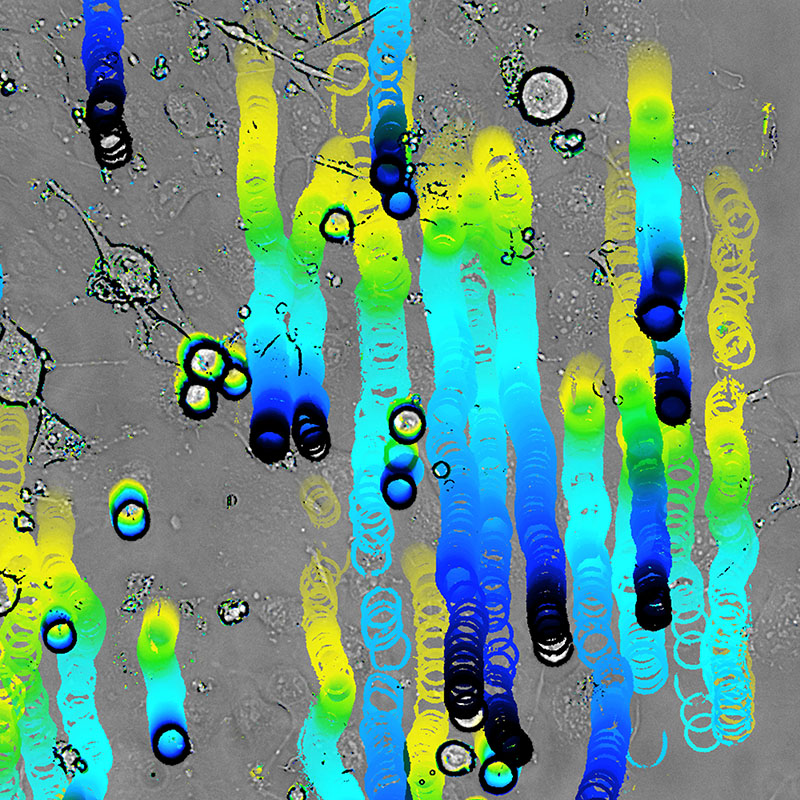

When inflammation occurs, immune cells migrate into the tissue. They roll along the vessel wall (passage of time from yellow to black) and attach to endothelial cells, so that they cannot be washed away by the flowing blood. Bright-field microscopy© Jana Zimmermann, Rupert Hallmann